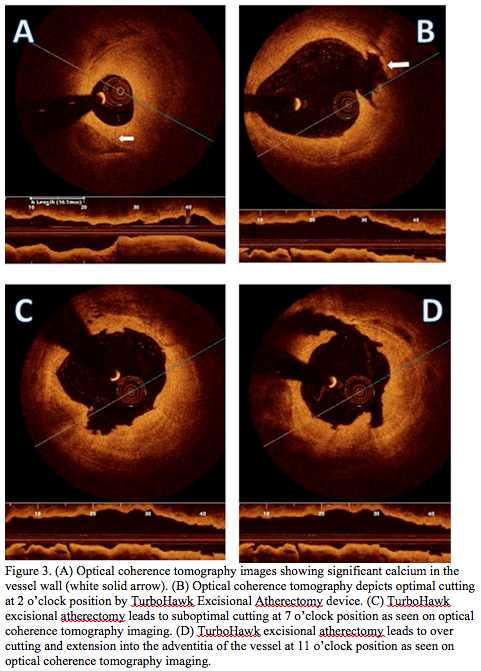

Interventional procedure. A 75 cm, 7 Fr sheath was placed in the right common femoral artery and then advanced to the left SFA using the up-over technique. Left SFA angiography revealed a heavily calcified and stenotic vessel with 1 vessel run-off (peroneal artery). A Whisper 0.014˝ guidewire (Abbott Vascular) was advanced to the distal left peroneal artery. After the left SFA lesion was predilated with a 2.5 x 40 mm Sleek balloon (Cordis Corporation), a 4 mm SpiderFX embolic device (eV3) was placed in the mid-left peroneal artery. FD-OCT images with the C7 Dragonfly catheter were obtained before and after excisional atherectomy (TurboHawk SX-C; eV3) and balloon angioplasty with a 4 x 120 mm Sleek balloon inflated up to 6 atm. A 6 x 120 mm Life Science stent (CR Bard) was then deployed in the SFA with excellent angiographic results (Figures 3A, 3B, 3C, and 3D).

Case #3 illustrates the use of FD-OCT imaging in a patient treated with excisional atherectomy. This approved technique is used to modify fibrocalcific lesions prior to balloon angioplasty with or without stent implantation. The TurboHawk uses a cutting blade that is manipulated under fluoroscopic guidance. In this case, FD-OCT depicts the therapeutic pitfalls and potential dangers of “blind cutting” of plaques. Unequal plaque removal is clearly demonstrated by FD-OCT in this case (Figures 3A, 3B, 3C, and 3D). The excessive excision of plaque and of the vessel wall in some segments nearly reached the adventitial layer, whereas plaque removal was clearly suboptimal in several other areas. New atherectomy devices with incorporated IVUS or OCT imaging capabilities could lead to better outcomes and fewer complications, ie, dissections, perforations, and vessel closures.